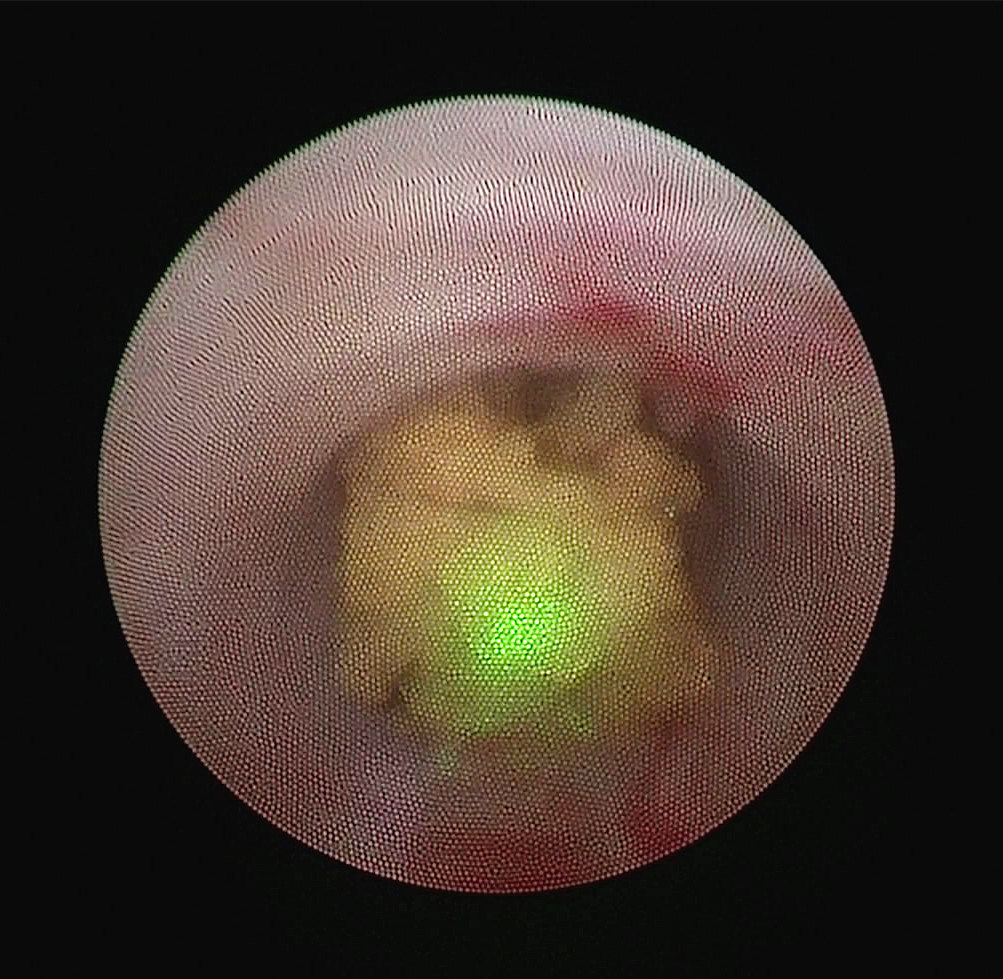

术中输尿管镜下寻及梗阻的输尿管结石

钬激光将大部分结石粉末化,留置支架管保护肾脏